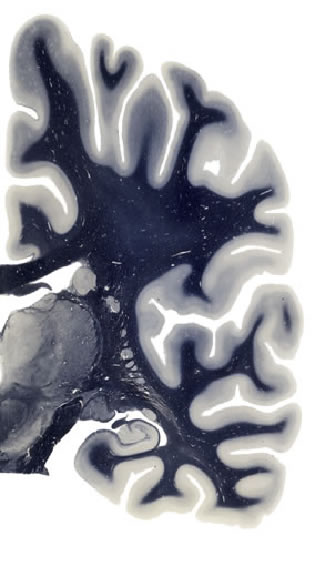

Hi-Resolution Sections · Cells (Nissl Staining) · Virtual Microscopy

Frontal sections (Nissl) from the Atlas Brain:

Slice ID:

r3-0450

Plate NR:

41

Position:

25,2 mm